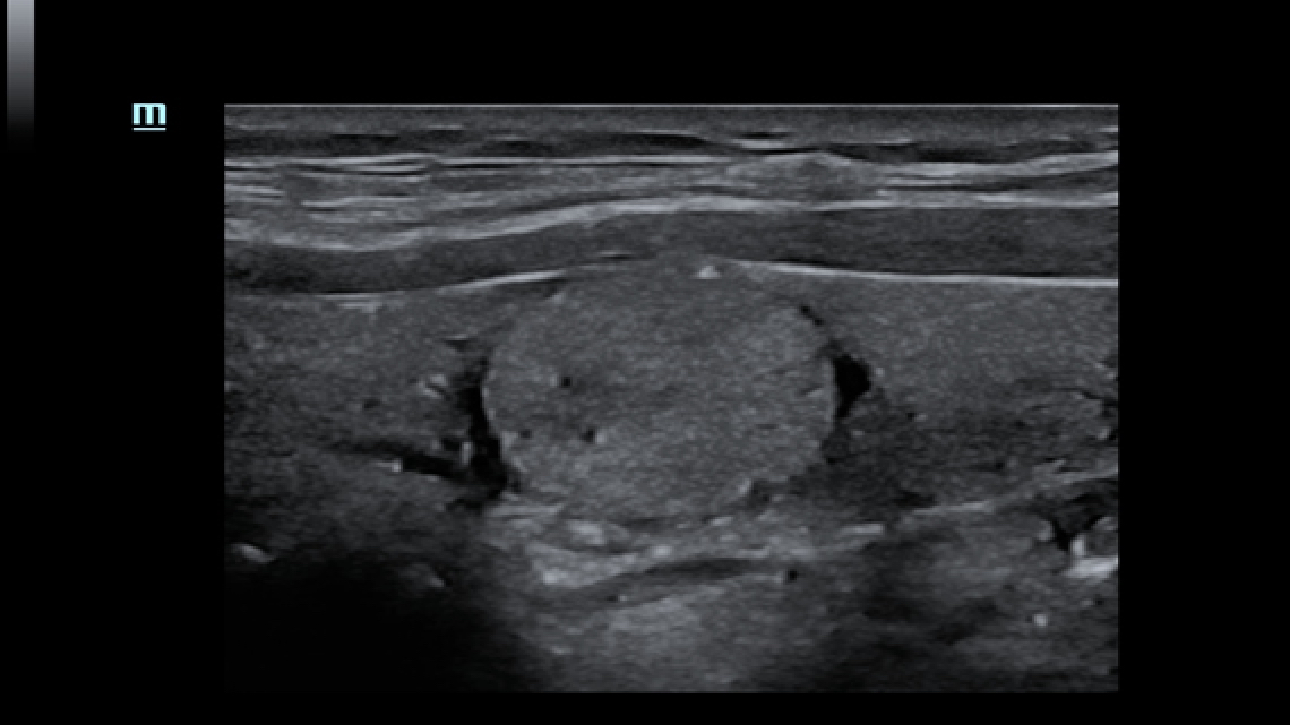

Clinical Images